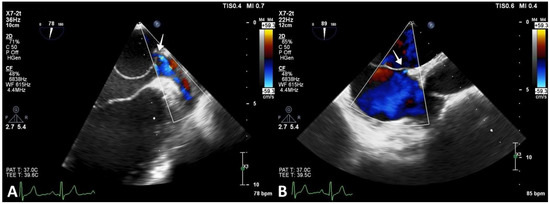

Multiple membrane fenestrations ensured the connection between the proximal and distal LA chambers. Color Doppler interrogation of the interatrial septum revealed PFO with minimal spontaneous left-to-right shunt (Figure 4).

Figure 4.

Transesophageal echocardiography revealing CTS. (A) Image showing openings in the CTS membrane (arrow). (B) PFO with minimal spontaneous left-to-right shunt (arrow).